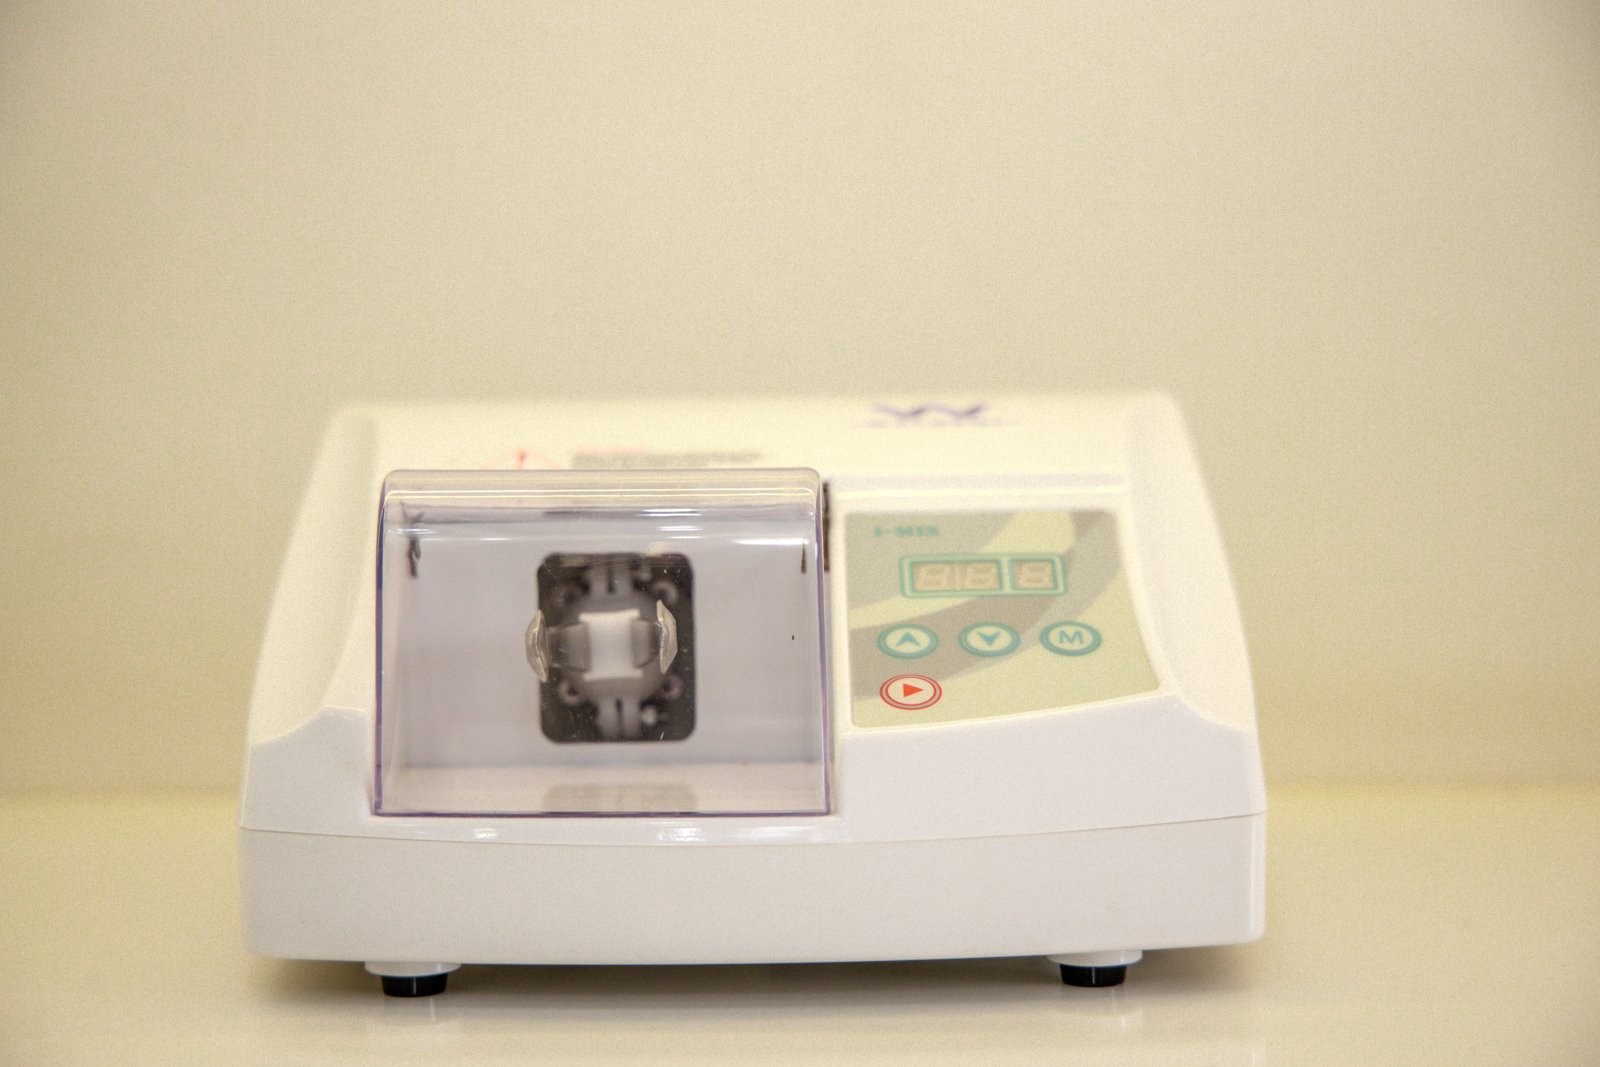

Specialized endodontic care to save infected teeth and relieve pain.

See every stage of our treatments with clear, step-by-step visuals that reflect our precision and care.